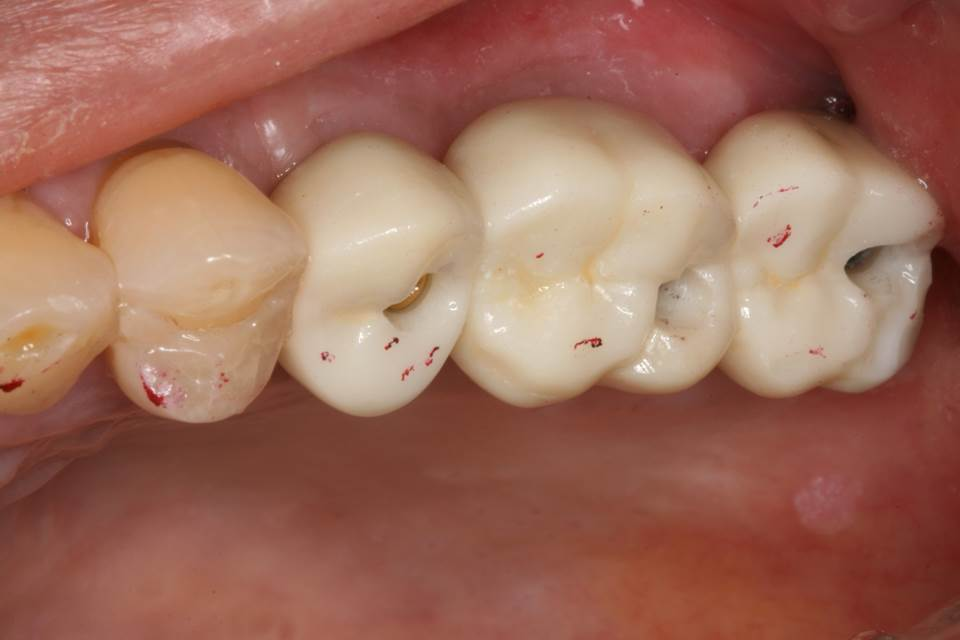

The final prosthesis (splinted monolithic zirconia crowns) was delivered after contact and occlusal adjustments.

Occlusal access holes (for SCRP prosthesis) were prepared at the fossa areas.

After final cementation with permanent resin cement and removal of the excess cement by removing the whole prosthesis.